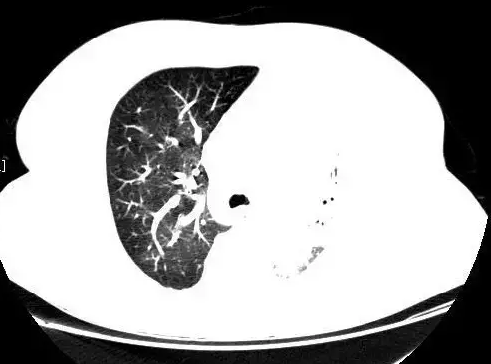

家住淮安金湖县的李阿姨从十几年前开始,经常出现阵发性咳嗽,一直没能查明病因。更糟的是在今年4月的一次体检中,李阿姨的CT片上竟完全看不到左肺。李阿姨和家人一同辗转多家医院想查明原因,最终在当地一家医院查出其胸骨后长了一个巨大甲状腺肿,拳头大小的肿块严重压迫着气管,医生怀疑这有可能是咳嗽多年的原因。

在术前评估中,省中医院的专家们发现病情有些奇怪。“虽然检查发现胸骨后确有巨大甲状腺肿并压迫了气管,但根据我们多年的临床经验,如此巨大甲状腺肿不至于引起患者咳嗽十几年,严重到CT片上看不到左肺影像。”普外科副主任医师戴洪山介绍说,“更加奇怪的是,患者左支气管入口处有金属影,不像之前其他医院认为的血管钙化影。

带着疑问,医生多次询问李阿姨,然而她一口咬定没做过肺部手术,也从没有误吞过异物。为了谨慎起见,医院组织放射科、呼吸科等多学科专家联合会诊,专家一致认为,患者左支气管内有1.5厘米的金属影,异物滑落的可能性很大。

术后,李阿姨恢复良好,出院前的CT检查显示,左肺又恢复了以往的功能,多年的咳嗽也消失无踪。